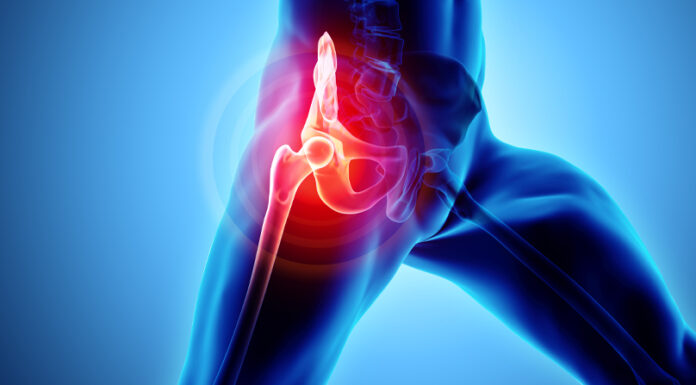

Σύγχρονες τεχνικές ολικής αρθροπλαστικής ισχίου

Η πιο συχνή μορφή αρθρίτιδας είναι η οστεοαρθρίτιδα, η οποία αφορά στη φθορά του χόνδρου που επικαλύπτει το οστό στην περιοχή που έρχονται σε επαφή δύο οστά. Συνήθως εμφανίζεται στα δάχτυλα του χεριού, στο ισχίο και στο γόνατο, ενώ ο πόνος που προκαλεί μπορεί...

Ολική αρθροπλαστική και στα δυο ισχία σε μια επέμβαση

Με τη χρήση του Ρομποτικού Συστήματος ΜΑΚΟ, πραγματοποιήθηκε επιτυχώς στο ΥΓΕΙΑ, σε μια χειρουργική επέμβαση, ολική αρθροπλαστική και των δύο ισχίων σε ασθενή 58 ετών με βαρεία οστεοαρθρίτιδα.

Πρόκειται για την εφαρμογή ταυτόχρονης ολικής αρθροπλαστικής ισχίου και στα δυο μέλη, που διενεργήθηκε στο ΥΓΕΙΑ, από...

Πόνος στο ισχίο: Ένα συχνό, σύνηθες αλλά και ύπουλο σύμπτωμα

Ο πόνος ή άλγος στο ισχίο είναι το συχνότερο σύμπτωμα που καλούνται οι ορθοπαιδικοί να αντιμετωπίσουν καθημερινά.

Άλγος στο ισχίο είναι ο πόνος που νιώθει ο ασθενής στην περιοχή του ισχίου κυρίως στην πρόσθια επιφάνεια αυτού αλλά και στην έξω όπως και στην οπίσθια επιφάνεια...